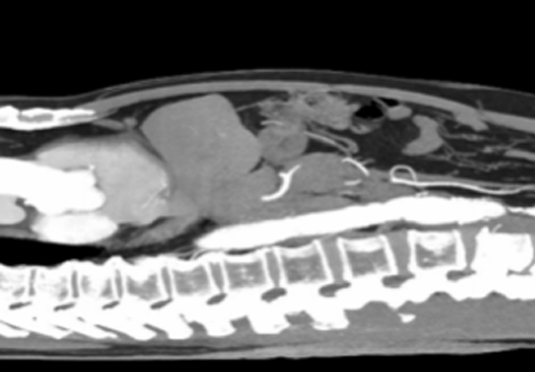

微創(chuàng)射頻消融術(shù)

適用于微創(chuàng)射頻熱消融術(shù)治療患者,引進權(quán)威醫(yī)療團體輔助引流。